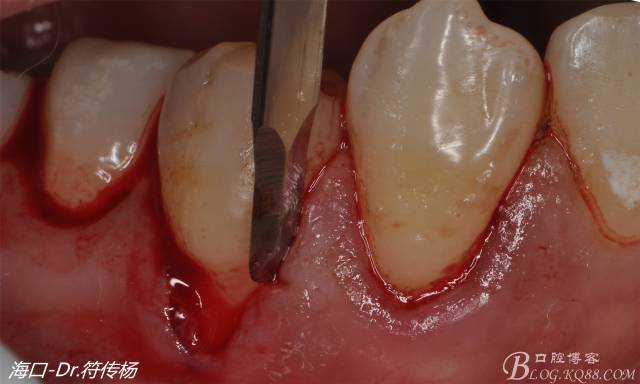

首先用顯微手術(shù)刀切斷手術(shù)范圍內(nèi)的牙周韌帶

然后使用下頜開隧刀剝離牙齦

最后使用牙齦乳頭分離器分離牙齦乳頭